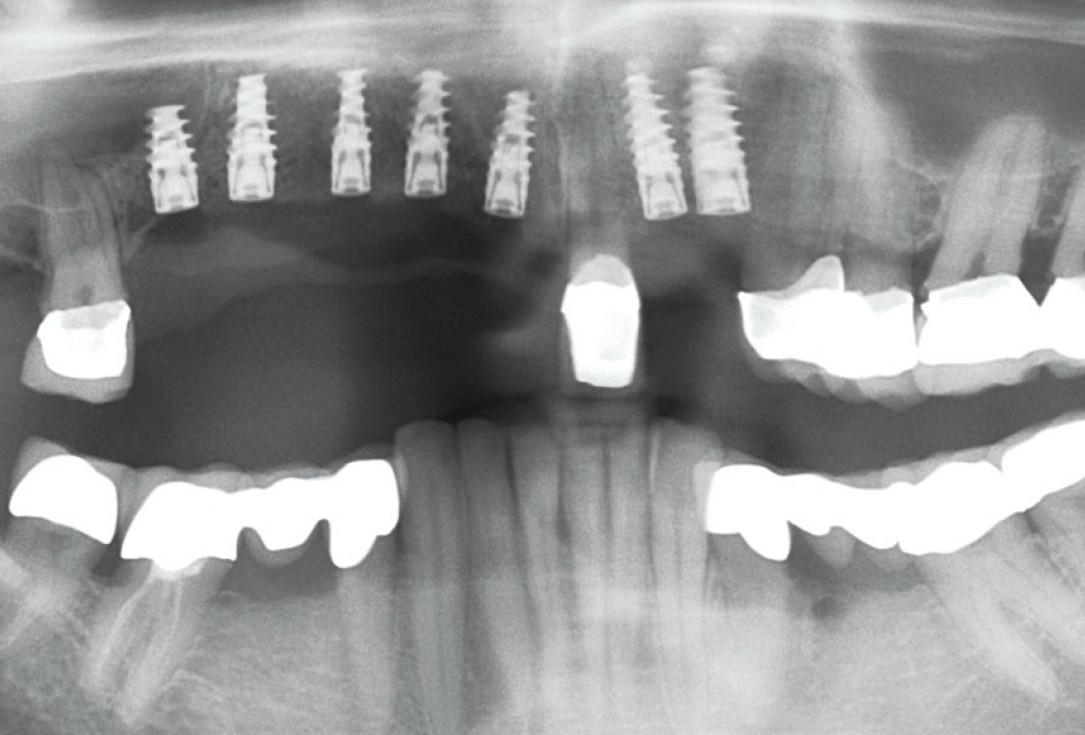

Full maxillary reconstruction with maxgraft® bonebuilder - Dr. C. Hilscher

Initial x-ray, ten years post implantationem alio loco, large peri-implant bone loss